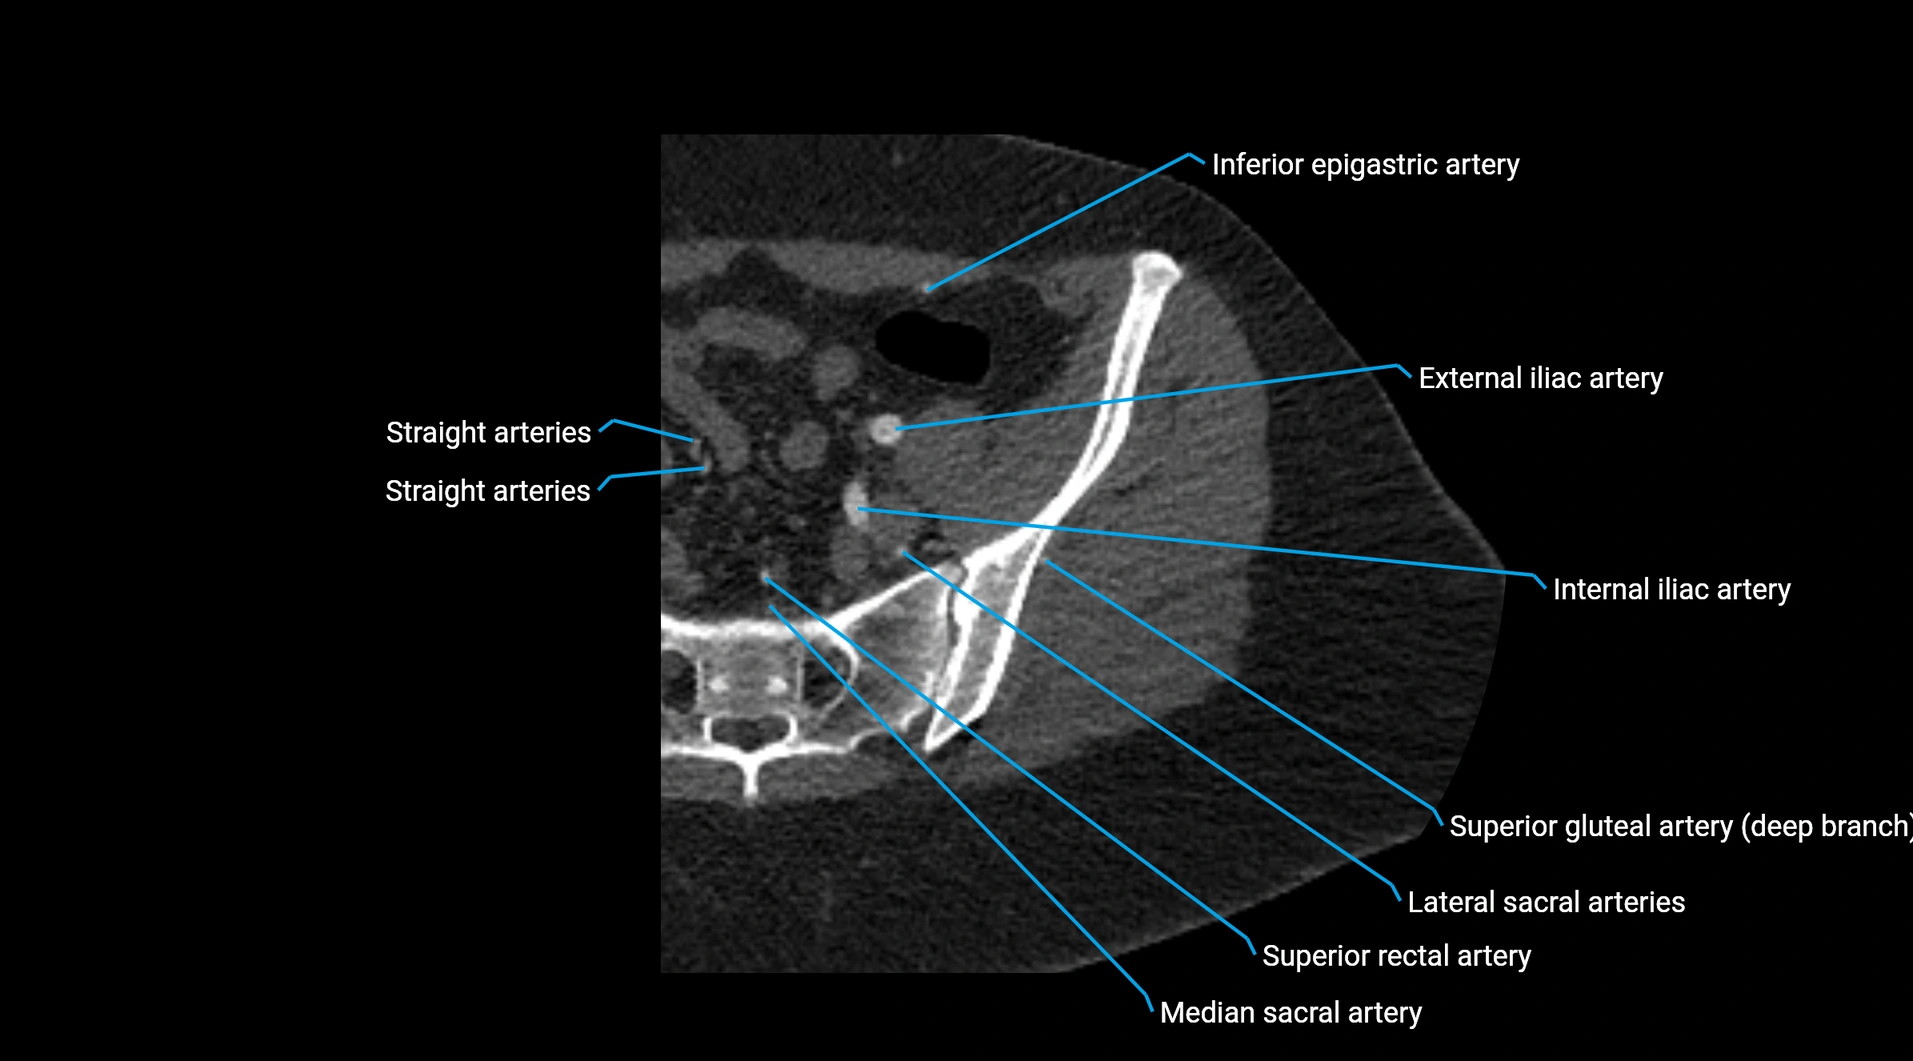

CT images

image

Contrast-enhanced CT (CTA):

• Gold standard for abdominal aortic imaging

• Provides excellent detail of lumen, wall, aneurysm, thrombus, and branch vessels

• Multiplanar and 3D reconstructions help in aneurysm measurement, stent graft planning, and dissection evaluation